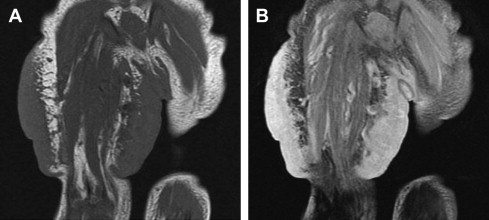

Congenital hemangiomas are tumors that have reached their maximal size at birth. Two variant forms of congenital hemangioma have been described: rapidly involuting congenital hemangioma (RICH) and noninvoluting congenital hemangioma (NICH). These lesions are distinguishable from infantile hemangioma by their clinical course, as described by their names. Unfortunately, these lesions cannot be reliably differentiated from common infantile hemangiomas based on imaging alone. However, some imaging features may be suggestive of a specific lesion. On ultrasonography, the useful differentiating factors are the presence of more visible vessels in congenital hemangiomas in comparison to infantile hemangioma, as well as the presence of intravascular thrombi, calcifications, vascular aneurysms, and arteriovenous shunting ( Fig. 3 ). RICH and NICH are less likely to be well defined than infantile hemangioma on MRI ( Fig. 4 ).